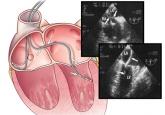

ArticleDetecting and managing device leads inadvertently placed in the left ventricleAuthor:Richard G. Trohman, MD, MBAPublish date: January 2, 2018How it happens, how to prevent it, how to detect and correct it immediately, and how to manage cases discovered long after.Read More